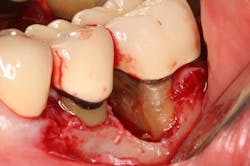

- Fractured calculus. Calculus can chemically bond to the hydroxyapatite crystalline structure of cementum, and that union can be stronger than the cohesive strength within calculus itself.9 When attempting to remove, the calculus can fracture and a basal layer remains firmly attached to the root. Repeated strokes with a scaling instrument result in a “burnished,” or smooth, surface that is often undetectable by a periodontal probe.

For a variety of reasons, dentists and hygienists may not be able to remove all the subgingival calculus and biofilm during scaling and root planing. This pathogenic ecosystem may not only be harmful to the individual tooth, but it can also be a source of the bacterial infiltrate found in the peri-implant environment.

A patient had four quadrants of scaling and root planing in the office of her general dentist. Subsequently, three maxillary anterior implants were placed. The patient was scheduled every six months for periodontal maintenance visits. Radiographs taken prior to the scaling and root planing (figure 4) revealed moderate periodontitis with slight vertical bone loss involving the mandibular left first molar. A deep vertical osseous defect on the distal of the second molar was present.